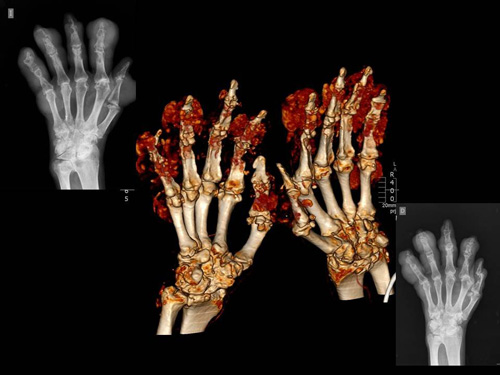

- Gota tofácea crónica: con el tiempo las crisis son más frecuentes y los periodos asintomáticos menores. La gota tofácea aparece como consecuencia de una incapacidad de eliminar el urato tan rápidamente como es producido y se acumula formando los llamados tofos.

La historia clínica y la exploración física por un reumatólogo son fundamentales aunque el patrón oro para el diagnóstico de gota es la demostración del depósito de cristales de urato monosódico por microscopía óptica de luz polarizada. Actualmente la ecografía músculoesquelética juega un papel importante en el diagnóstico indirecto y permite ayudar en la monitorización del tratamiento.